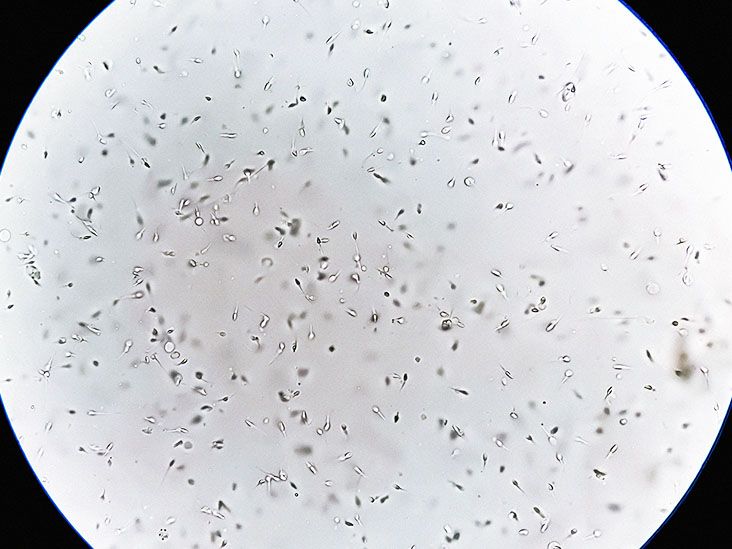

לזרע יש מיקרוביום משלו, וחוסר איזון חיידקי עלול להשפיע על ספירת הזרע ואיכותו, על פי מחקר חדש. החוקרים מצאו רמות